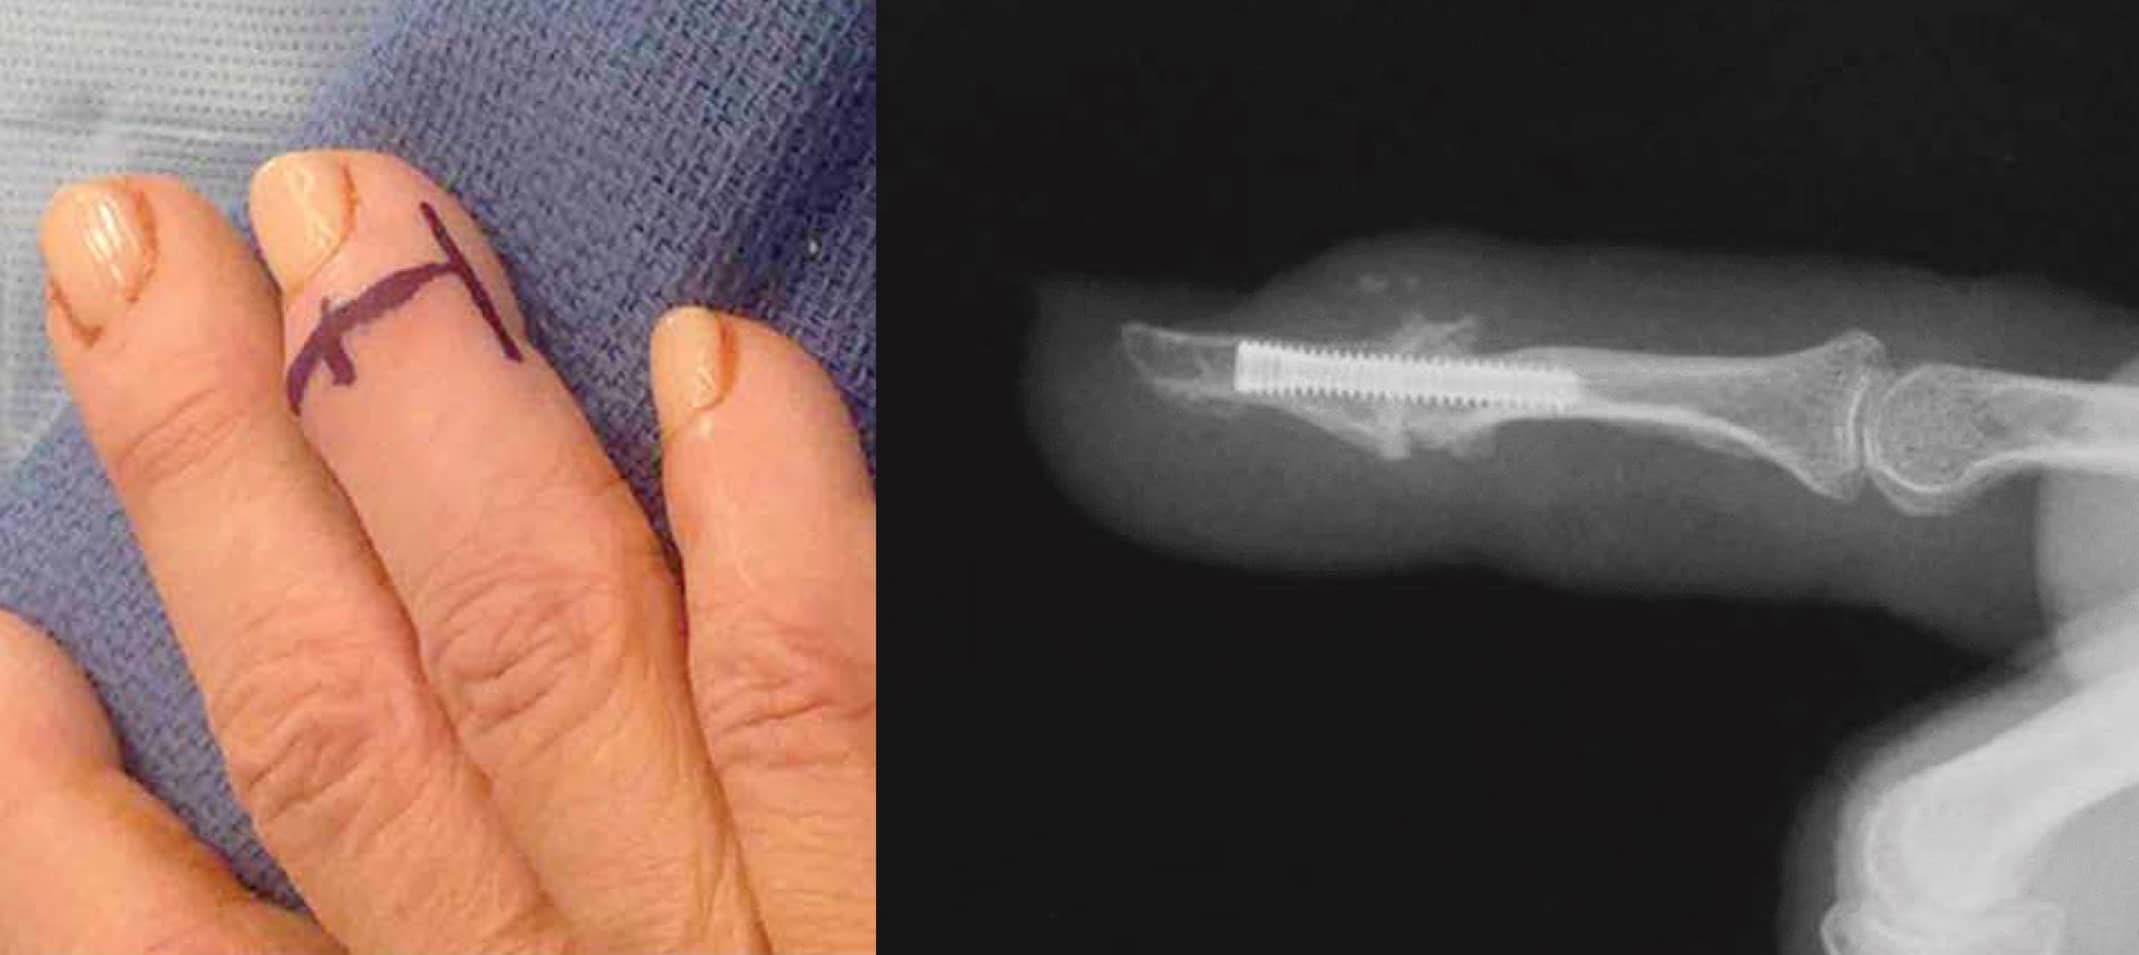

Photos Showing Finger Marked for Fusion and Post-Fusion X-Ray

(Left) Finger marked for a planned skin incision for a distal interphalangeal (DIP) joint arthrodesis (fusion). (Right) Finger following distal interphalangeal (DIP) joint arthrodesis (fusion) with a headless compression screw. The screw is buried under the bone.

Reproduced from Beldner S, Polatsch DB. Arthrodesis of the Metacarpophalangeal and Interphalangeal Joints of the Hand: Current Concepts. J Am Acad Orthop Surg. 2016;24(5):290-297. doi:10.5435/JAAOS-D-15-00033